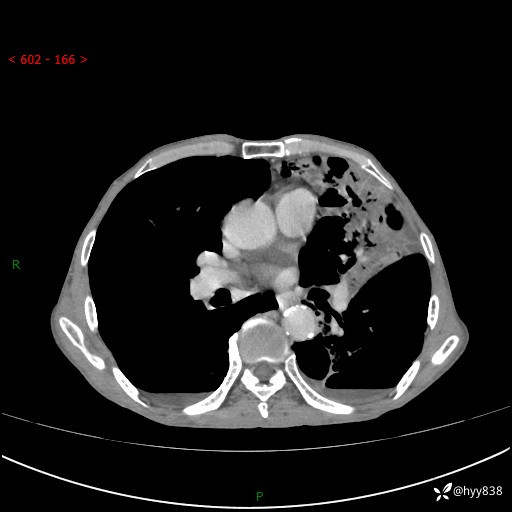

胸部CT平扫+增强